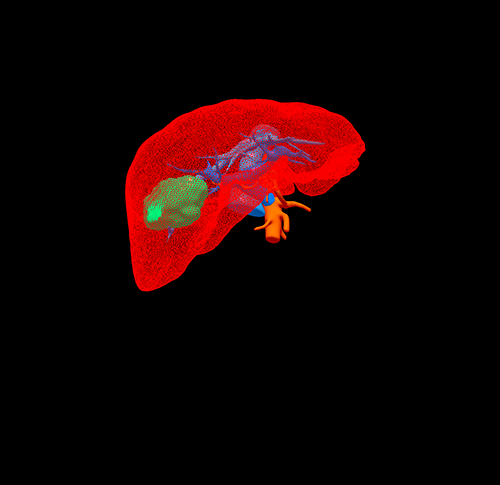

S6肝癌 胆囊结石--腹腔镜右肝部分切除 胆囊切除